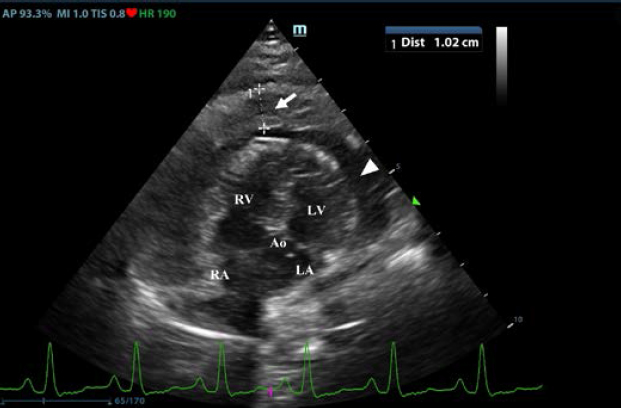

First, transthoracic echocardiogram findings were a small amount of circumferential tamponating pericardial effusion (Fig. 1) and a severe hyperechoic pericardial thickening (10.2 mm) (Fig. 2). The right atrium was normal in size and there was collapse during systole. There was mild septal flattening seen on short axis view of the left ventricle. A short-axis left ventricular M-mode showed posterior displacement of the interventricular septum during late diastole at the time of atrial systole (Fig. 3). The epicardium and pericardium had a hyperechoic appearance with a thin, shaggy layer of heterogeneous echogenic material lining the surface of each (Fig. 1, Supplementary Video I). Pericardiocentesis was not recommended at this time given that the patient was minimally clinically and hemodynamically affected. Few hours later, a second echocardiographic examination, after stabilization of left ventricular volume with intravenous (IV) lactate ringer solution at maintenance rate, showed a worsening of pericardial thickness (13 mm) and an increase in pleural effusion. Furthermore, there was a >25% mitral inflow variation noted with respiration. In addition, there was >30% tricuspid inflow variation with respiration, signs of CP. During the second echocardiography, the patient appeared to be slightly dyspneic due to the increased thoracic effusion.

Fig. 1. Transthoracic echocardiogram – right parasternal long-axis four-chambered view. Note the pericardial effusion, the right atrial collapse (white arrow), the thickened, hyperechoic pericardium, and the scant pericardial effusion (white arrowhead). LA: left atrium; LV: left ventricle; RA: right atrium; and RV: right ventricle.

Supplementary Video I. Transthoracic echocardiogram – right parasternal long-axis four-chambered view. Note the thickened, hyperechoic pericardium, the pericardial effusion, and the hyperechoic appearance of the epicardium and pericardium with a thin, shaggy layer of heterogeneous echogenic material lining the surface of both. The left ventricular chamber appears empty, and the walls are pseudohypertrophic.